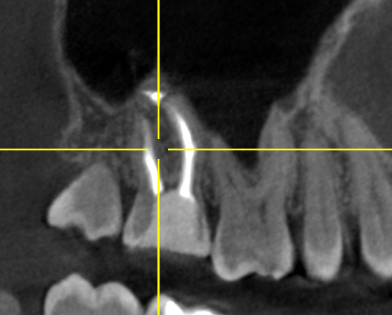

Клинический случай: пациент 54 года обратился для планового осмотра, ранее лечился в другом городе. На снимке КТ выявлена киста, которая пациента не беспокоила, однако являлась причиной хронического воспаления в полости рта. Зуб ранее уже был лечен.

Проведено эндодонтическое лечение по протоколу.

Киста на многокорневом зубе (зуб 17)

На контрольном КТ спустя 6 месяцев полное заживление воспалительного процесса (кисты). Пациент направлен к ортопеду для восстановления зуба коронкой. Врач Белым Елена Сергеевна.